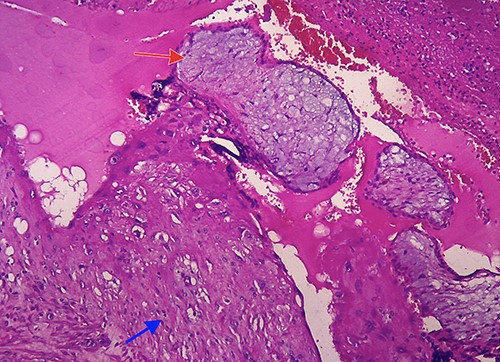

Histopathological examination confirmed the diagnosis of cesarean scar pregnancy (red arrow = necrotic villi chorealis; green arrow = fibromuscular tissue and blue arrow = necrotic tissue).

Microscopic image (hematoxylin and eosin, 40×) showing villi chorealis embedded in fibromuscular tissue (red arrow: villi chorealis and blue arrow: fibromuscular tissue).